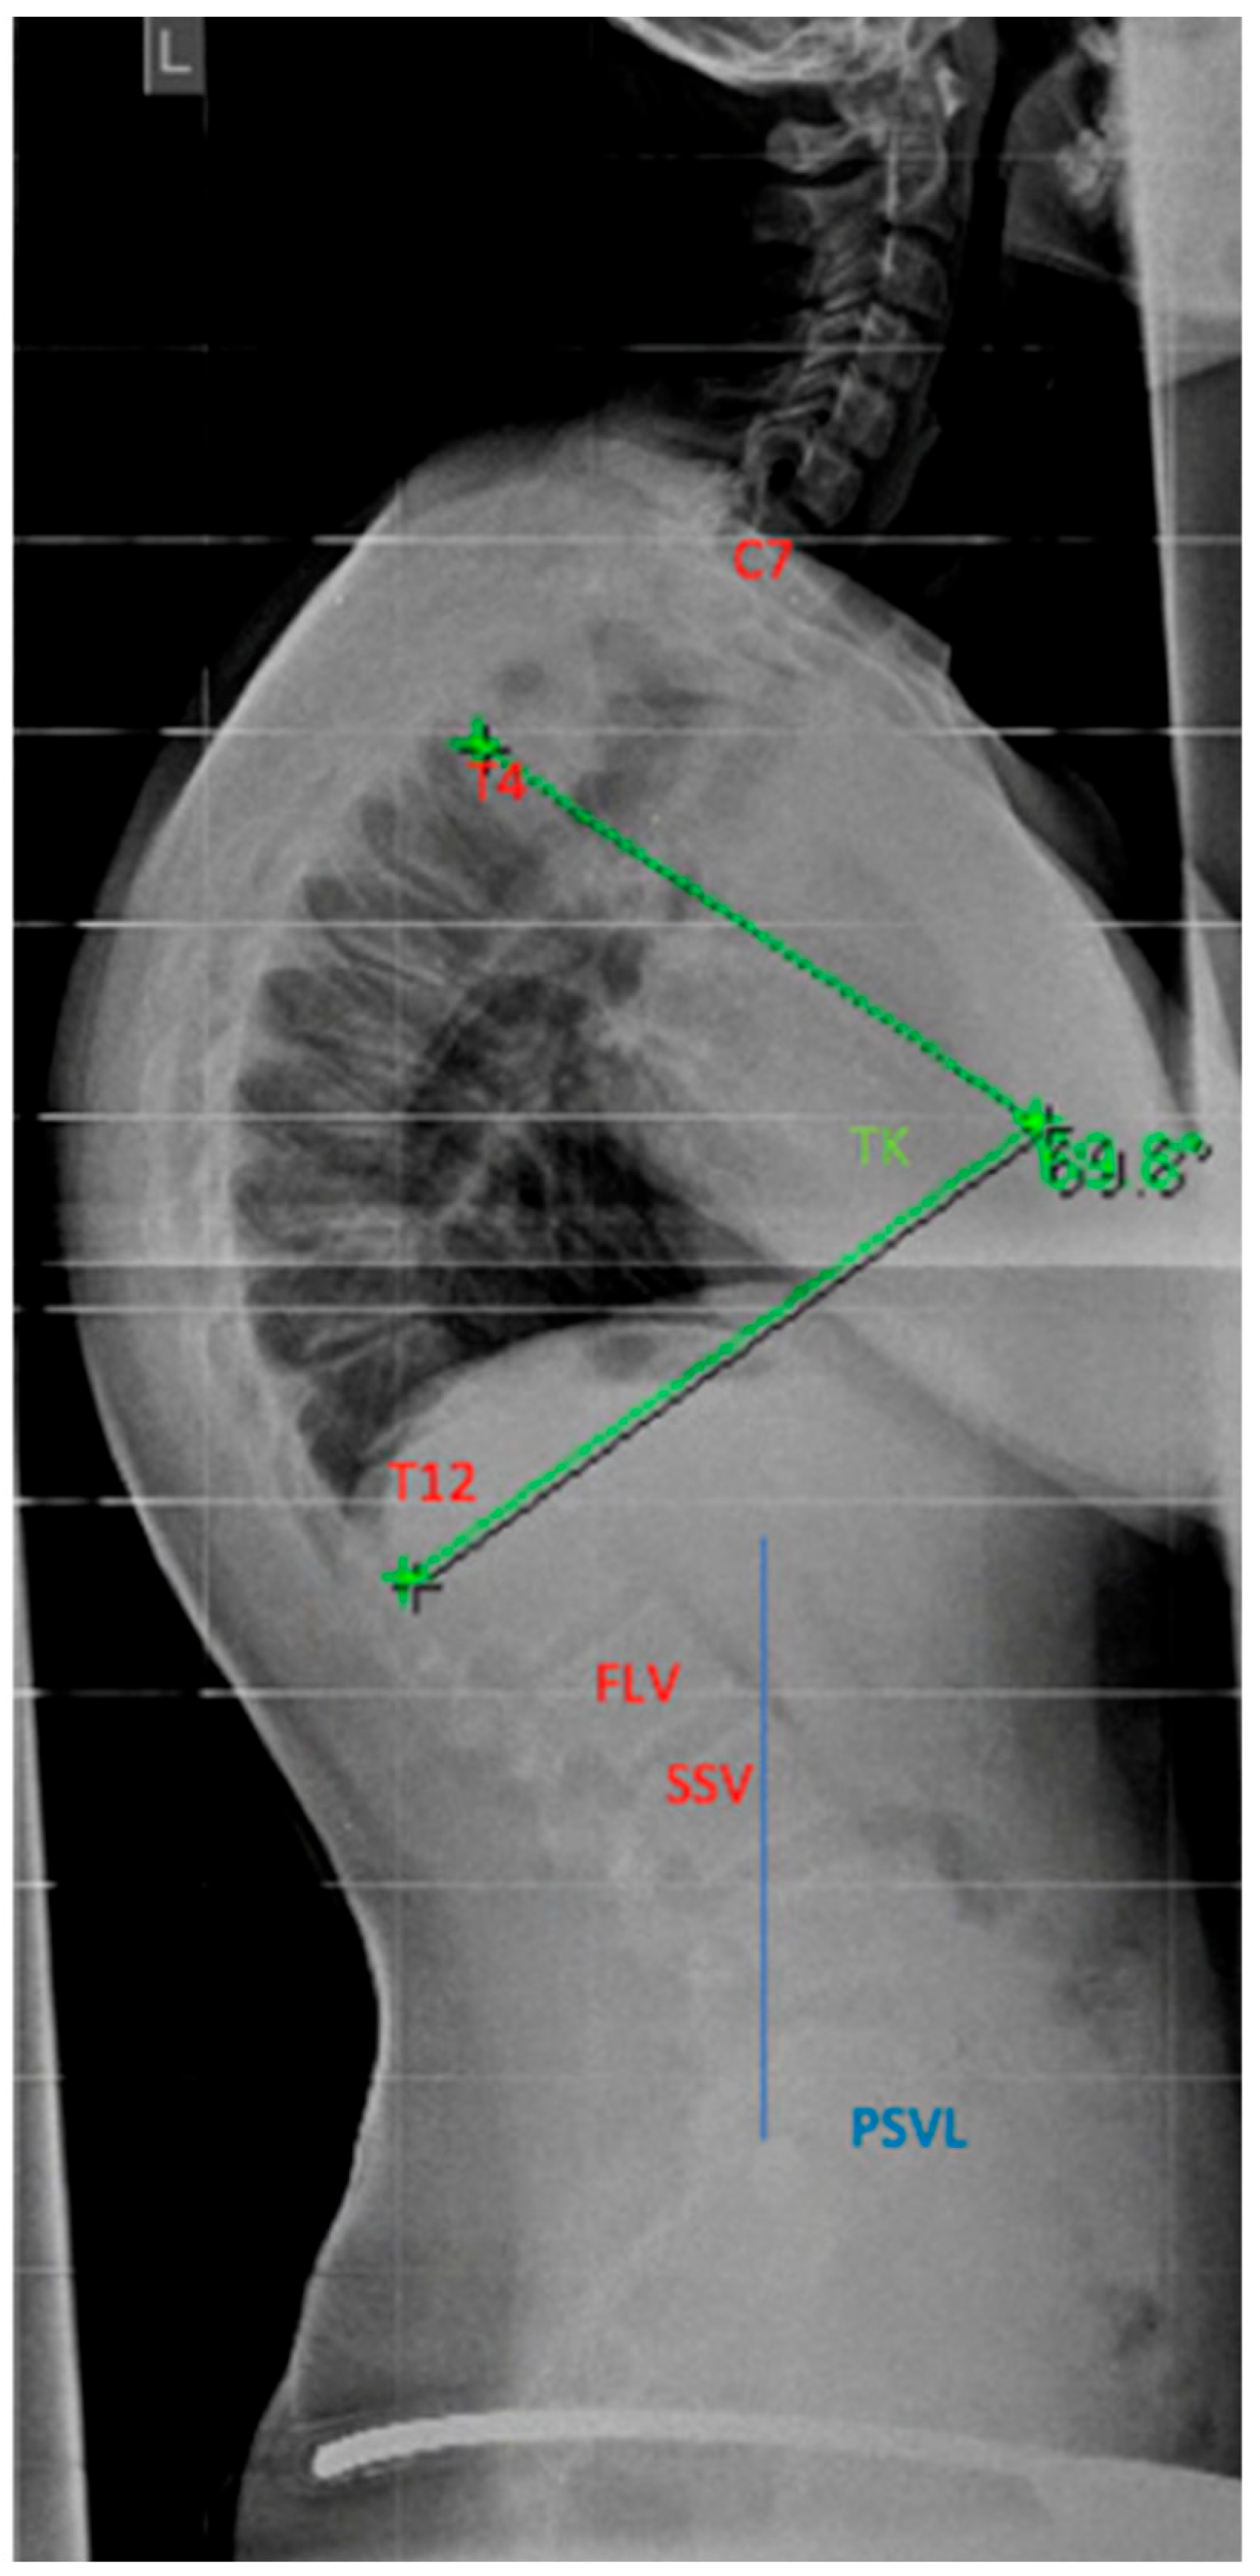

4.2. Diagnostics

Although initially described by Sorensen, the definition of SD has been definitively established by subsequent work by Edgren et al. and Blumenthal et al., with SD typically manifesting mostly in the thoracic spine (type I) and less commonly in the lumbar spine (type II) [79,85,86]; see Figure 7. The measurement of thoracic kyphosis according to Cobb (Th1–Th12) is sometimes difficult on conventional X-rays due to the humeral heads, so the Stagnara angle (Th4–Th12) is a reliable alternative (Figure 8). In children with SD, back pain and a positive family history are common, and clinical examination typically reveals a gibbus and a flexible deformity. In addition to a detailed medical history, a thorough physical examination is of utmost importance. The various signs and findings typical of SD are listed in Table 2.

4.4.1. Selection of the Instrumentation Range

The determination of the instrumentation range is certainly dependent on the chosen surgical procedure. The upper instrumented vertebra (UIV) is usually the proximal vertebra that still belongs to the curvature [104]. The selection of the lowest instrumented vertebra (LIV) can be the first lordotic vertebra (FLV) or the sagittal stable vertebra (SSV) according to Cho et al. [105]; see Figure 12. However, in the meta-analysis by Gong et al., instrumentation of the SSV proved to be superior to the FLV [106]. In this meta-analysis, the incidence of distal junctional kyphosis (DJK) in SD was reported to be 20.8%, and of these cases, 27.8% of patients had to be revised; 5.9% of the SSV cohort and 43.6% of the FLV cohort developed DJK [106].

Figure 1. Examples for determination of growth potential according to Sanders of ne non-dominant left (L) hand [21]. (ac) and Risser [22] (df), (a)—Sanders 2, (b)—Sanders 3, (c)—Sanders 5, (d)—Risser 0, (e)—Risser 2, (f)—Risser IV.